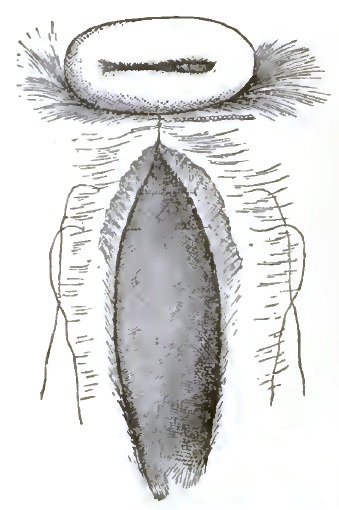

| 26. | IMPERFORATE HYMEN |

| 27. | SIMS'S VAGINAL DILATOR |